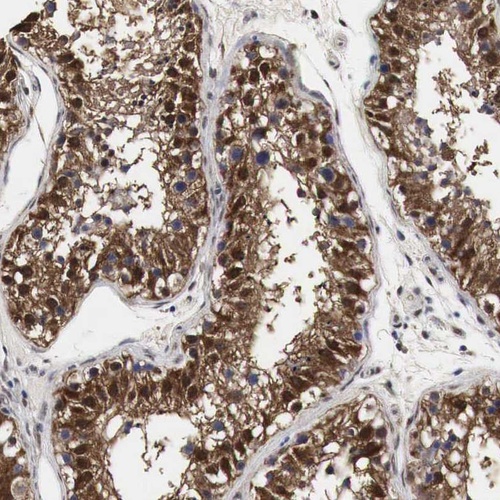

Immunohistochemical staining of human testis shows strong cytoplasmic and nuclear positivity in cells in seminiferus ducts.